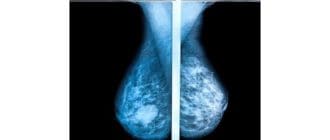

トモシンセシスまたはデジタルトモシンセシスは、乳癌をスクリーニングするための新しいタイプのマンモグラムである。これは比較的新しい技術であり、一部の病院でのみ利用可能です。このスクリーニング手順の初期の結果は有望である。 […]